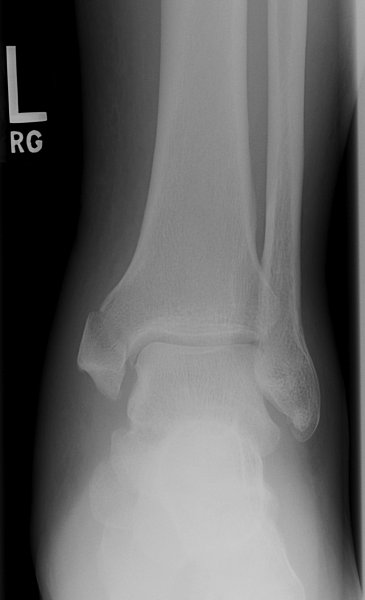

Return to Medial Malleolus Fracture